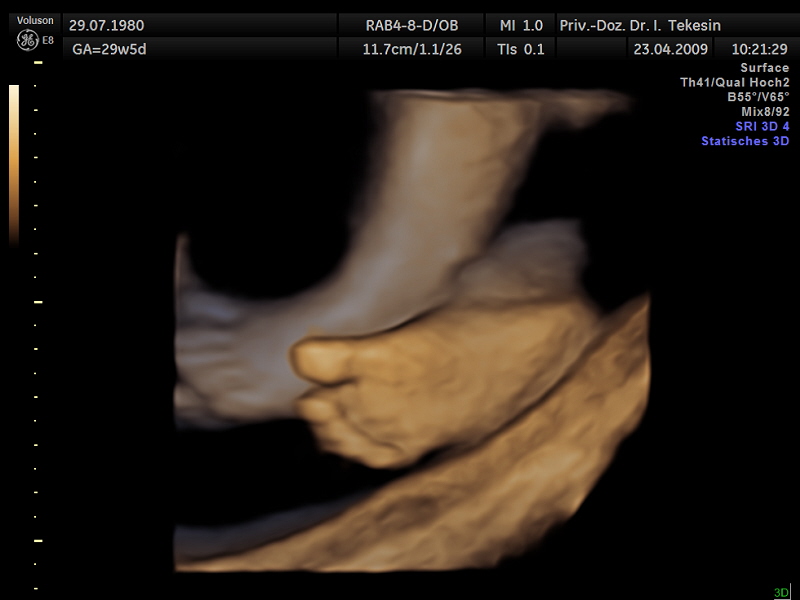

Kind in der 28. Woche (3D-Darstellung)